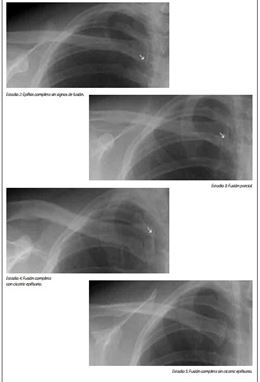

Lo explica a Europa Press la presidenta de Fundación Raíces, Lourdes Reyzábal, para denunciar «lo injusto» de un sistema en que «la palabra del fiscal» y unas pruebas médicas que tienen un margen de error superior a dos años y cuya validez ha sido cuestionada entre otros por el Defensor del Pueblo, se imponen «por encima del interés superior del menor» cuando se trata de niños extranjeros que están solos en España.

Se trasladó a Madrid buscando más suerte, como explica Reyzábal. De nuevo, la policía lo encontró durmiendo en la calle y por su apariencia física, ya que no portaba ninguna documentación, asumió que era menor de edad y lo trasladó al centro de menores de Hortaleza. Desde allí se dio aviso al fiscal que de nuevo, ordenó pruebas médicas, esta vez en el Gregorio Marañón, y concluyó que tenía más de 18 años.

El otro adolescente, que ahora tiene 17 años, tuvo un recorrido similar pero sin pasar por Barcelona. Llegó a Madrid estando solo hace dos meses y tras pasar por el centro de menores de Hortaleza y por las pruebas médicas de determinación de la edad, se quedó igualmente en la calle con un decreto del fiscal que decía que era un adulto. Tampoco tenía en aquel momento documentación original de su país que probase lo contrario.